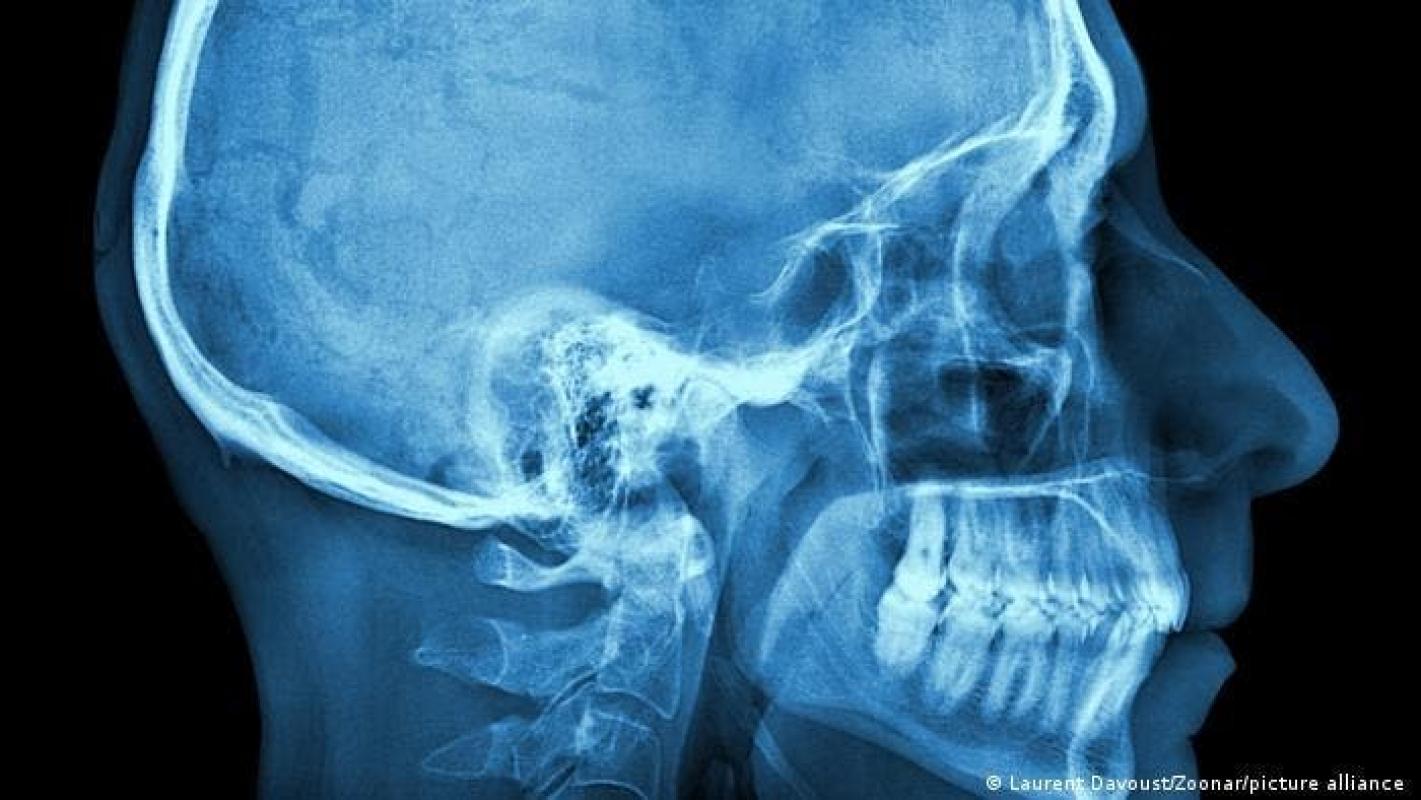

Mediante un análisis de más de dos docenas de cabezas humanas, entre ellas la de un sujeto vivo y la de 12 cabezas conservadas en formaldehído, los investigadores dirigidos por Szilvia Mezey, del Departamento de Biomedicina de la Universidad de Basilea, y el profesor Jens Christoph Türp, del Centro Universitario de Medicina Dental de Basilea (UZB), identificaron la tercera capa "anatómicamente distinta" del músculo masetero.

Esta capa, muy profunda, va desde la apófisis cigomática –proyección ósea que forma parte de los "pómulos" y que puede palparse justo delante de la oreja– hasta la apófisis coronoides –proyección triangular en el maxilar inferior–.